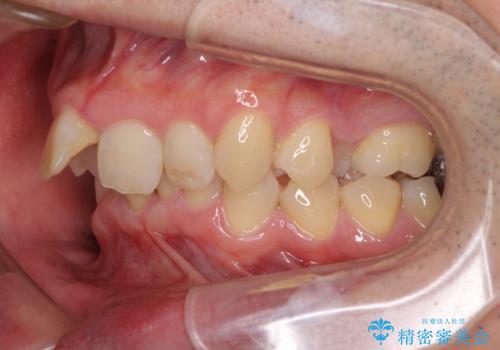

- ぶつけて前歯が折れてしまったとのことで来院された患者様です。

折れてしまった前歯は軽傷であり、歯内の歯髄に影響は及んでいませんでした。

通常では速やかにオールセラミッククラウンにて補綴治療を行うのですが、デコボコしている歯列も気になっていたため、事前に矯正治療を行うこととしました。

上顎歯列の叢生が著しかったため、上顎左右第一小臼歯2本を抜歯し、目立たないワイヤー装置にて治療を進めることとしました。